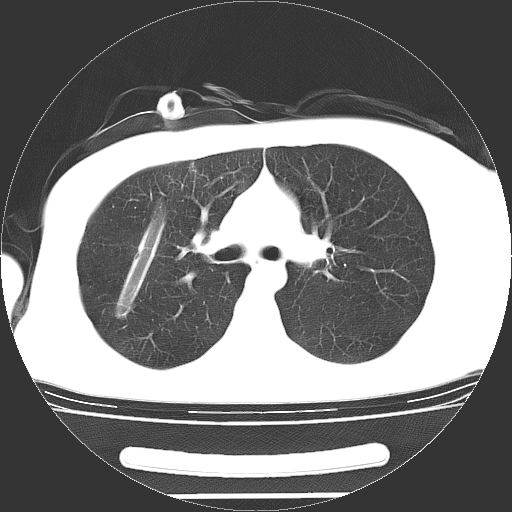

男,20岁,右侧气胸行闭式引流术后五天ct检查看肺内是否有肺大泡,纵隔窗未见异常,未上传。

1)右侧胸腔闭式引流术后导管留置。2)右肺未见肺大泡。

未见肺大泡,还有微量气体。